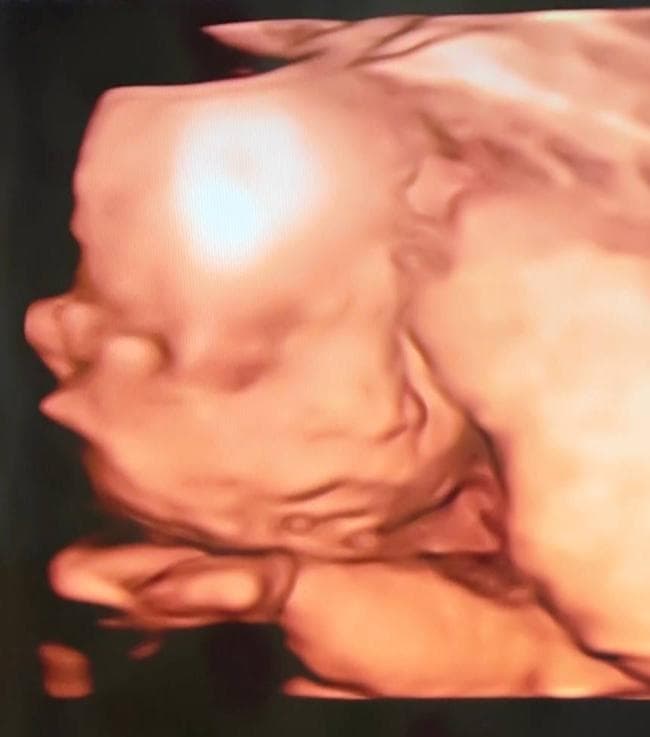

3장 모두 같은 날 촬영한 24주차 딸의 입체 초음파 사진입니다.

위 태아 사진을 보면 눈사이거리가 좀 멀어보입니다.

(다른 태아들 사진을 검색해보면 대부분 더 좁아보이더군요.)

위 프로필대로 저나 아내는 눈사이거리가 평균이라 이 부분이 의아합니다.

그리고 다른 의사선생님이 보시기에 태아의 코 크기나 콧볼 크기는

다른 태아들과 비교해서 평균인지, 아니면 크거나 작은지 궁금합니다.

아기 초음파 사진을 보면, 입체 초음파가 태아의 얼굴을 입체적으로 보여주지만, 아직 아기의 얼굴 형태는 많이 변할 수 있습니다. 24주차는 아직 아기의 외형이 성숙해지는 중이고, 얼굴 특징이 점차적으로 달라지기 때문에, 아기마다 얼굴의 비율이나 특징이 조금씩 다를 수 있습니다.

눈사이 거리나 코 크기 등은 아기의 유전자와 성장 단계에 따라 달라지기 때문에, 다른 아기들과 비교했을 때 차이가 있을 수 있습니다. 또한 입체 초음파 사진은 각도나 해상도에 따라 다르게 보일 수 있어, 다른 아기들 사진과 정확하게 비교하는 것은 어려울 수 있습니다.

태아의 얼굴 크기나 특징은 시간이 지나면서 점차 발달하고 성형되는 과정이므로, 걱정할 필요는 없습니다. 담당 의사가 건강 상태를 문제 없이 평가하셨다면, 크게 염려하지 않으셔도 될 듯 합니다. 초음파는 그저 발달 상태를 파악하는 수단일 뿐이니, 아기의 건강이 중요하다는 점을 기억하시고 마음 편하게 기다리세요.